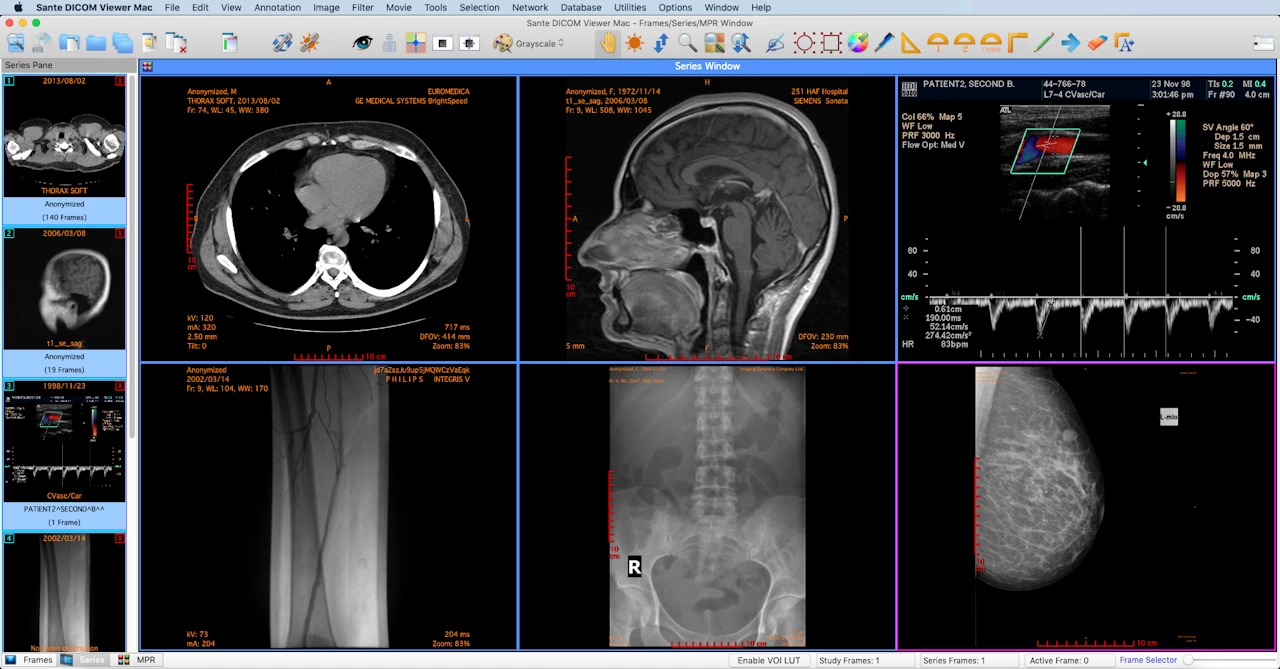

DICOM Viewer

DICOM viewers are the client used by medical professionals to analyze and examine test results. These DICOM viewers usually receive or retrieve a DICOM sample, and display the images and metadata it keeps. This is the main business logic and requirement of the DICOM process, because it is here where the images are looked at and examined, and the patient is medically diagnosed.

Medical professionals view and analyze medical images using a DICOM viewer client.